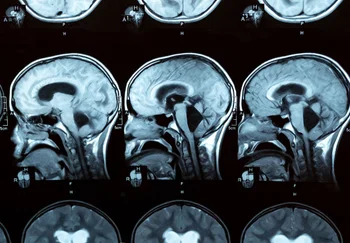

Исследователи снова «встряхнули» нейронауку — и, кажется, нашли ещё один тревожный звоночек, который может предсказать надвигающийся когнитивный закат при болезни Альцгеймера. Давайте разберёмся, кто и с кем там поссорился в мозгу, и почему это важнее, чем количество кальция в овсянке по утрам. Болезнь Альцгеймера — это тот ещё коварный вор: приходит незаметно, подкрадывается к памяти, мышлению и поведению, перечёркивая всё, что делало нас «нами». В 70% случаев, когда говорят о деменции, подразумевают именно Альцгеймера. Причина — скопление в мозге белковых залежей: бета-амилоид превращается в бляшки, тау-белок — в клубки. Они настолько мешают общению между нервными клетками, что даже самый упёртый мозг рано или поздно сдаётся на милость судьбы. На ранних этапах человек просто что-то забывает, но постепенно стирается всё: от воспоминаний до умения ориентироваться в пространстве и словарного запаса. А потом начинаются эмоциональные американские горки: апатия, раздражительность, тревожность — полный комплект бесплатного приложения к Альцгеймеру. Главное — возраст, но в команде риска и гены, сердце, да ещё образ жизни. Но подвох в том, что мозг начинает портиться задолго до того, как первые признаки проберутся наружу. Учёные под руководством Диего-Мартина Ломбардо решили поискать очень ранний маркер Альцгеймера — и заподозрили в этом одну странную «ссору» между двумя главными сетями мозга. Знакомьтесь: сеть пассивного режима (DMN) и дорсальная сеть внимания (DAN). Первая любит расслабляться, мечтать, ковыряться в себе и предаваться внутренним монологам — почти как мы в пятницу вечером. Вторая отвечает за внимание к миру, цели, фокус и внешние раздражители. Обычно это идеальные соседи с забором друг от друга: если DMN пришла в себя, DAN отдыхает, и наоборот. Когда одна заглушает другую — всё работает, как дорогие швейцарские часы. Но в долгосрочном исследовании с участием 182 человек (средний возраст — 70, мужчины — почти 60%) команда нашла тревожный признак: там, где оба признака Альцгеймера — и когнитивные провалы, и амилоидные залежи — сеть DMN и её внимательный сосед DAN уже не ссорятся как раньше. Их антикорреляция «сдувается», и мозг теряет привычный баланс. Это как если бы два злейших кота, наконец, сели на один диван — и стало совсем тревожно. Эта странная дружба (или безразличие) двух сетей оказывается мощным предсказателем ухудшения когнитивных способностей — даже если учесть возраст, пол, образование, и другие белковые пакости вроде тау. Оказалось, что даже университетский диплом тут не помогает: учёная степень, как щит от слабоумия, — это миф (по крайней мере, в этой схеме), и образование не спасает, когда DMN перестаёт конфликтовать с DAN. Учёные подозревают: если между DMN и DAN уходит напряжённость, значит, в мозге зарождается особый механизм краха когнитивных функций, не связанный напрямую с тау-белком и другими обсуждаемыми факторами, вроде запаса прочности (именно так называют способность мозга компенсировать старение и травмы — «когнитивный резерв»). Но не спешите радоваться или паниковать: доказать, что именно нарушения в работе DMN и DAN становятся причиной Альцгеймера, пока не удалось. Может быть, это только следствие печального процесса, а не его источник — нужна ещё целая гора исследований. Тем не менее, такой биомаркер — это шаг к тому, чтобы ловить вора на пороге, когда он только подкрадывается к нашему разуму, а не тогда, когда он уже унёс всё ценное. И пусть у мозга ещё много тайн, теперь у нас появился шанс — если не выиграть войну, то хотя бы попробовать подготовить оборону заранее.